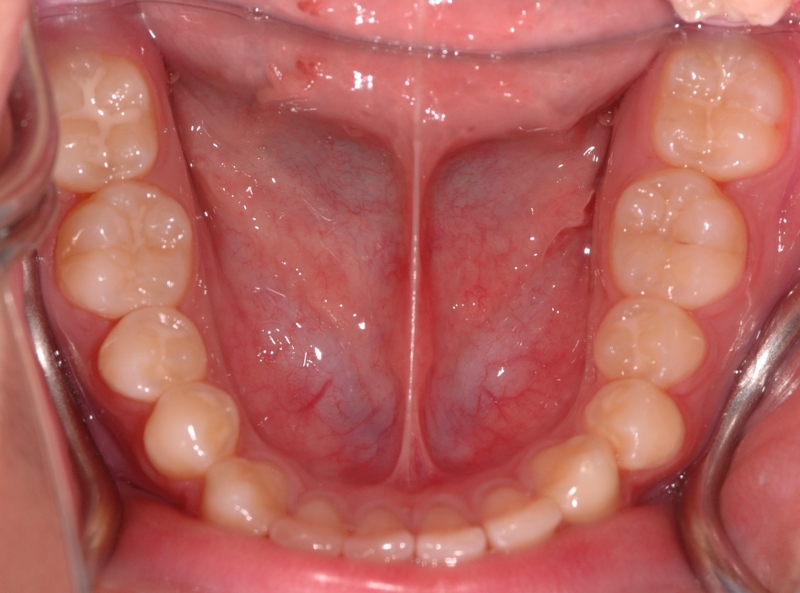

眼見為憑? 肉眼全看不見、牙一點也不痛  竟有14顆蛀牙!

年輕學子面對接二連三的考試壓力,除了身心疲憊引發的相關症狀,若因長期準備大考而忽略口腔檢查,可能因小失大!近期就有一名李姓高中生因為感覺門牙有輕微疼痛,就診後赫然發現即使外觀全無異樣,但全口已有多達14顆齲齒,得花更多時間和精力補牙,讓他苦笑著說,真是得不償失。念華牙醫診所李楊鈞醫師指出,青少年容易在念書過程中忽略口腔清潔,例如邊K書邊吃零食但未徹底潔牙,口腔健康往往在此進入高風險期。因此提醒不論男女老少、勿忘天天「愛牙四守則」:首要是每半年進行一次口腔檢查,才能及早發現口腔問題,遠離惱人的牙痛;此外,早晚使用含氟牙膏刷牙、每天使用牙線(棒),及吃完、喝完嚼無糖口香糖或使用含氟漱口水都是日常口腔保健的不二法門。早一步發現口腔問題,不方便潔牙時先咀嚼無糖口香糖幫助日常口腔保健,就不怕齲齒悄悄找上門!

李楊鈞醫師進一步說明,口腔健康若出狀況,初期不見得會有明顯病徵,但口腔健康是身體健康的重要基石,不能不多留心呵護。建議家長從小培養孩子正確的口腔保健觀念與習慣,萬萬不可忽略定期口腔檢查。以此患者為例,在國小時有家長的充分照顧,得以維持牙齒健康,國中後因為課業忙碌,一方面疏忽口腔衛生,另一方面只在乎表面美觀而沒有定期回診,時隔三年因為門牙齲齒回診,雖以肉眼完全察覺不出齲齒問題,但在全口X光檢查下即發現多達14顆齲齒。李楊鈞醫師表示,觀察國內年輕學子的讀書習慣,多會邊讀書邊食用含糖飲料或零食,且時間可能長達數小時。口腔在食用甜食後五分鐘內就會立刻變成酸性環境,讓蛀牙菌有機會侵蝕牙齒珐瑯質、開始脫鈣,大幅提升齲齒機率。民眾若輕忽吃完喝完後確實潔牙,一不小心就會釀成大問題,把握飲食後10分鐘的黃金潔牙時間,養成正確潔牙習慣,才能保護口腔健康。